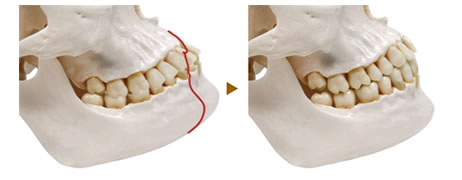

このような場合は上下のアゴを後退させて、オトガイと呼ばれるアゴ先を前に出してエステティックラインを整えます。口の中からの手術で完璧なフェイスラインを形成します。

上顎左右第1小臼歯と歯槽骨を切除して、後方に移動するための骨の隙間を作ります。出来たすき間を利用して前歯6本がくっついている骨をひと塊として後方に移動させ、PLLA吸収性プレート、骨折用ステンレスワイヤー、チタンプレートで固定します。位置決めで大切にしている点は、鼻柱の高さや角度、鼻翼形態(小鼻の広がり)歯の傾き(歯軸傾斜)、後方移動量、ほうれい線の有無、くちびるの形、下の歯の傾き(歯軸傾斜)、咬合関係(噛み合わせ)、前歯である、下顎中切歯、側切歯、犬歯(特に犬歯が横方向へ動いあ場合の当たり方(側方干渉)です。